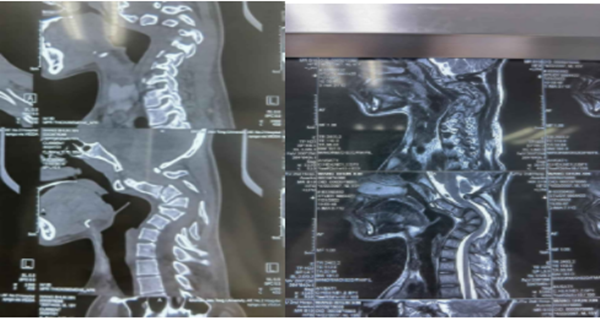

据文献报道,颈椎后凸≥30°即称为重度的颈椎后凸畸形,并且在颈椎过屈过伸时后凸角度改变小于50%称为僵硬性后凸畸形。而该患者,其后凸角度达到110°,且在过屈过伸位置上后凸角度几乎没有变化。对于这种严重且僵硬的颈椎后凸畸形,手术的目的不光是解决畸形的问题,同时还需完成脊髓的减压,给受损的脊髓神经根创造恢复的空间。然而手术的风险和困难也来源于此,在矫正僵硬颈椎畸形时,会在短时间内使颈椎以及脊髓的空间位置发生剧烈的改变,在这一过程中,如何避免原本脆弱的脊髓张力增加而导致四肢瘫痪,是一个严重而极富挑战性的难题。这么严重的畸形,国内外都没有成熟的治疗标准,国内也仅仅几家大医院开展过类似手术,而且只是零星的个案报道。李浩鹏主任医师团队结合这个患者特点,详细评估每张影像学资料,为患者制定了术前牵引,手术先前路松解,再后路截骨固定,再次前路固定的周详的治疗方案。

经过周密的术前准备后,由骨二科李浩鹏主任医师主刀,王国毓副主任医师、杨宝辉副主任医师、徐思越副主任医师,程志坚及卢腾主治医师配合,手术经过仰卧—俯卧—再仰卧,两次翻身,共8个小时,最终顺利完成。手术的成功离不开麻醉科李芳教授团队、手术室张新侠老师团队以及骨二科神经电生理监护黄亚娟、孙丽君老师的保驾护航。术后第二天,患者就可以在家人搀扶下下床活动。